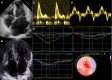

Restrictive cardiomyopathy (RCM) is a heterogeneous group of diseases characterized by restrictive left ventricular pathophysiology, i.e. a rapid rise in ventricular pressure with only small increases in filling volume due to increased myocardial stiffness. More precisely, the defining feature of RCM is the coexistence of persistent restrictive pathophysiology, diastolic dysfunction, non-dilated ventricles, and atrial dilatation, regardless of ventricular wall thickness and systolic function. Beyond this shared haemodynamic hallmark, the phenotypic spectrum of RCM is wide. The disorders manifesting as RCM may be classified according to four main disease mechanisms: (i) interstitial fibrosis and intrinsic myocardial dysfunction, (ii) infiltration of extracellular spaces, (iii) accumulation of storage material within cardiomyocytes, or (iv) endomyocardial fibrosis. Many disorders do not show restrictive pathophysiology throughout their natural history, but only at an initial stage (with an evolution towards a hypokinetic and dilated phenotype) or at a terminal stage (often progressing from a hypertrophic phenotype). Furthermore, elements of both hypertrophic and restrictive phenotypes may coexist in some patients, making the classification challenge. Restrictive pathophysiology can be demonstrated by cardiac catheterization or Doppler echocardiography. The specific conditions may usually be diagnosed based on clinical data, 12-lead electrocardiogram, echocardiography, nuclear medicine, or cardiovascular magnetic resonance, but further investigations may be needed, up to endomyocardial biopsy and genetic evaluation. The spectrum of therapies is also wide and heterogeneous, but disease-modifying treatments are available only for cardiac amyloidosis and, partially, for iron overload cardiomyopathy.